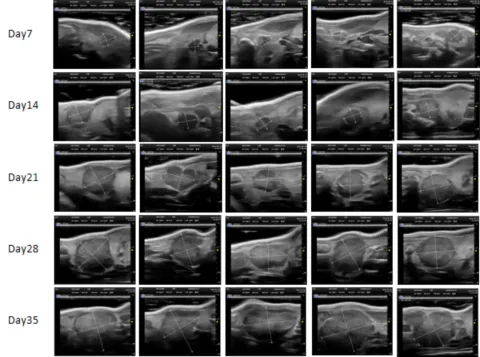

PDX Model (Growth Curve)